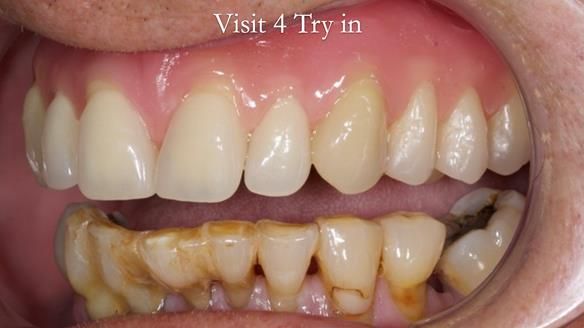

Welcome to my Newsletter 54 showing the making and fitting of dentures (a complete upper metal reinforced denture, a lower immediate partial denture and a definitive Scandinavian designed, metal based lower partial denture) for David, a 75 -year-old man. The full protocol workflow is presented including the use of dentate photographs to mimic his natural teeth.

Interestingly we found that the upper complete denture when finished and fitted didn’t have good enough retention for David’s satisfaction. It was relined by adding compound to the buccal flanges – to almost overextend into the sulcus to ‘create’ a sulcus, followed by using a light bodied silicone impression material. This improved the function of the C/-considerably. A lower Scandinavian hygienically designed lower RPD was also provided which helped with occlusal stability and reseating the upper denture – further improving the fit.